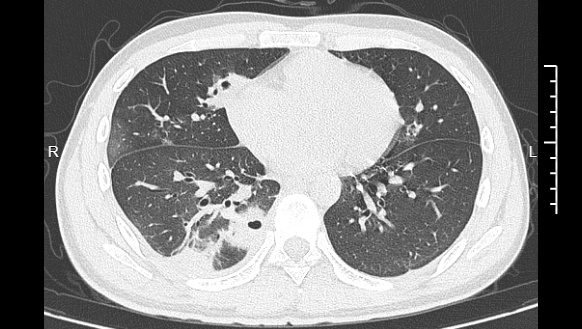

熬到第三天,小林烧至39℃就医,经检查,确诊为血源性肺脓肿,其肺部已有十几个空洞,部分肺组织还发生了坏死。

后续细菌培养和基因检测发现,小林血液中检出皮肤表面常见的金黄色葡萄球菌。医生解释,这颗痘痘长在脸部“危险三角区”,未清洁就挤痘的压力将细菌推入血管引发败血症,细菌随血流侵入肺部侵蚀组织,这才是致病根源。